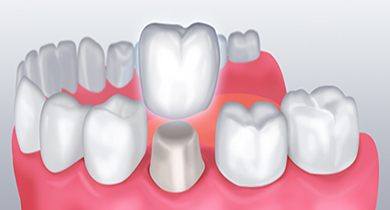

치아가 파절되었거나 충치부위가 광범위한 경우 치아 모양의 본을 떠

크라운을 제작한 후 씌우는 치료를 진행합니다.